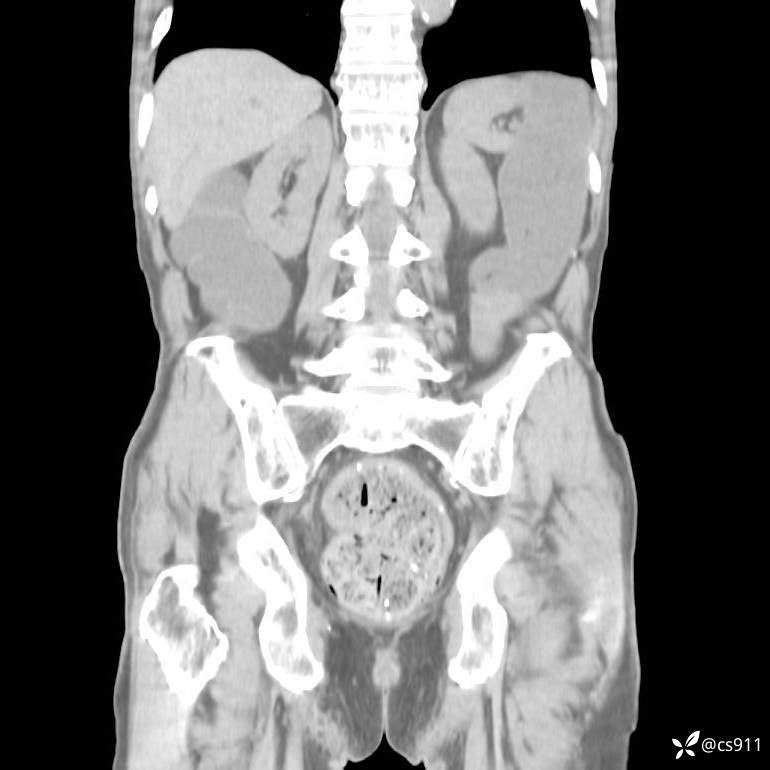

急腹症之急诊CT,原因?答案公布

男,77岁,腹痛、腹胀伴恶心呕吐1天。呕吐胃内容物,非喷射性呕吐,有咖啡色样胃内容物,诉有胃穿孔病史。查体:全腹平,下腹部压痛,全腹无反跳痛,叩诊呈浊音,移动性浊音阴性,肠鸣音减弱,1-2次/分。肛检:直肠未扪及明显肿物,可触及大量粪块。

T 36.6℃ P 80次/分 R 26次/分 BP 100/60mmHg

白细胞(WBC) H 14.55 10e9/L 4-10

中性粒细胞百分率(NEUT%) H 85.7 % 40-75

血淀粉酶(AMY) HH 1859 U/L 35-135

癌胚抗原(CEA) H 27.44 ng/ml 0-5

呕吐物 潜血试验 * 阳性 阴性

患者轮椅入室检查神志清楚, 能配合摆位和呼吸